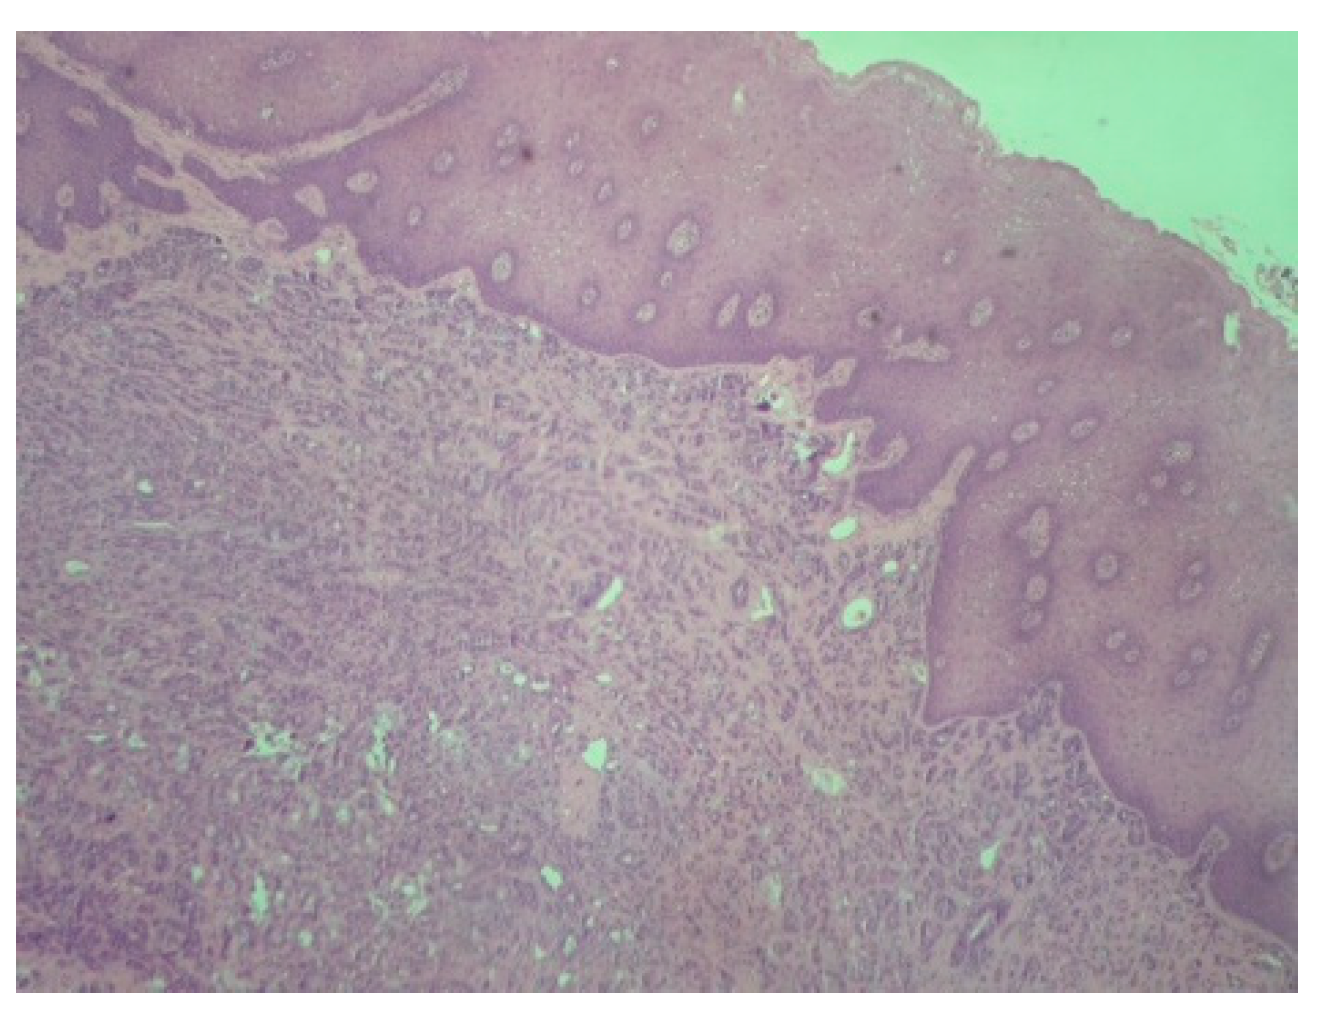

Figure 2.

Polymorphous adenocarcinoma: Tumor cells with infiltrative growth pattern in lamina propria. Note the intact overlying squamous epithelium (H-E ×100).